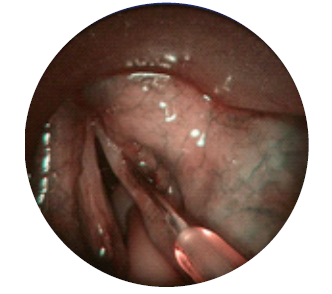

Injeção intralesional, preferencialmente na lâmina própria superficial (fig. 2).

Foi submetido a uma nova microcirurgia laríngea com recurso a LASER de CO2, com uma potência de 5 watts e modo superpulsed. As áreas afetadas foram injetadas com 12,5 mg (0,5 mL) usando uma agulha laríngea (fig. 2). A análise histopatológica confirmou papilomas de células escamosas. O procedimento foi repetido após três e seis semanas.